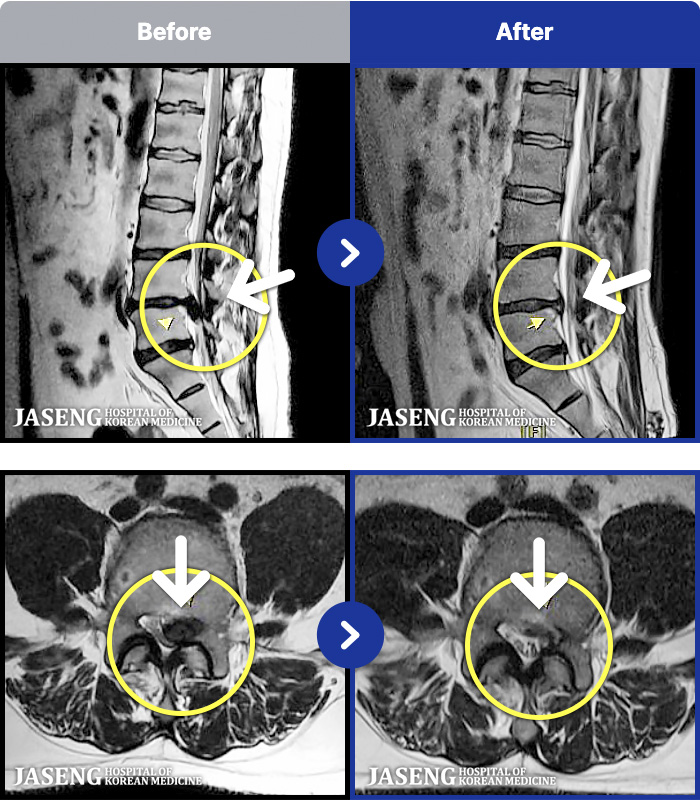

MRI ġ

1,240 MRI ũ ʸ Ȯϼ.